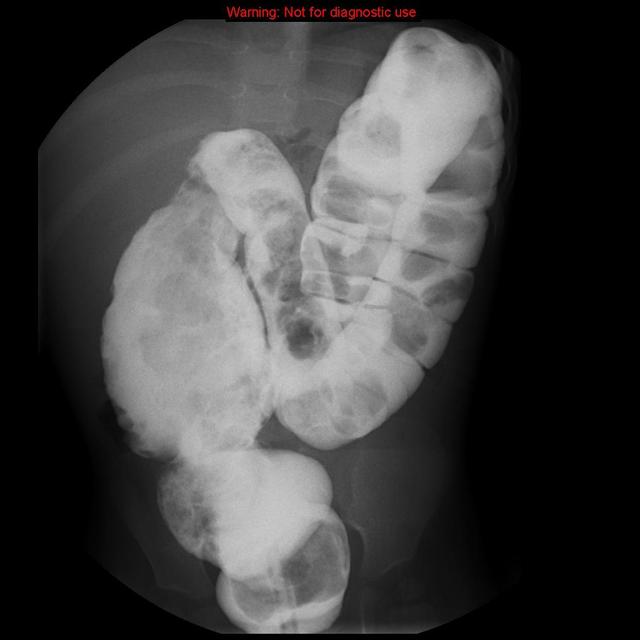

图 4 X 线钡灌肠检查所见近端结肠蓄便、肠壁肿胀,扩张。病变证实为先天性巨结肠

图 3 X 线正位片显示大肠扩张其内充满粪便类混杂密度影,其上方肠道扩张积气